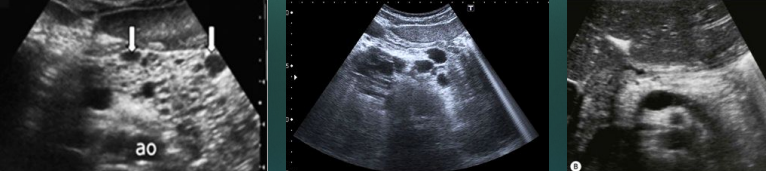

Acute pancreatitis with stone obstructing the pancreatic duct

Describe this image

Diagnosis?

Gallbladder with wall thickening and a stone obstructing the common bile duct causing dilatation (posterior shadowing). Results in pancreatitis

Dx: gallstones/pancreatitis

Transverse view of the pancreas

Pancreas appears to be swollen/enlarged with increased echogenicity and has peripancreatic fluid

Dx: acute pancreatitis

Transverse image of pancreas

Pancreatic parenchyma appears hyperechoic with echogenic foci (calcifications) throughout.